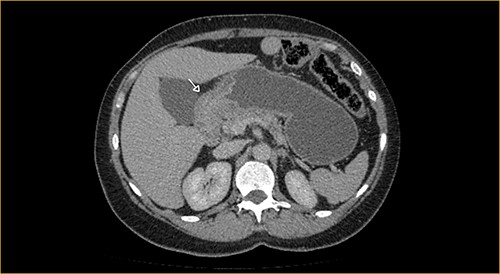

Laboratory examination showed anemia. An excluded stomach distention and parietal thickening of the pylorus and antrum were identified during abdominal computed tomography (CT) and magnetic resonance imaging (Figs 1–4). Thoracic CT was normal.

Portal phase transversal section image on CT showing excluded stomach distention with parietal thickening of the pylorus and antrum (arrow).